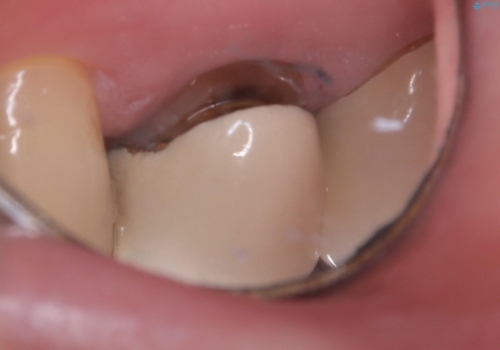

- 主訴:いつも物が詰まる場所があり気になる。衛生士に被せものと土台の境目に汚れが溜まっている箇所があると指摘され気になっている。

過去に入れた被せものと土台の歯との適合が悪く、隙間が出来ておりそこに汚れが溜まりやすい状態になっていました。セラミッククラウンでのやり替えとなりました。

唇側マージン不適なこと説明し、審美性・適合性に優れたセラミッククラウン(スタンダード)でのやり替えとなりました。

治療途中、一度仮歯に置き換えを行っています。